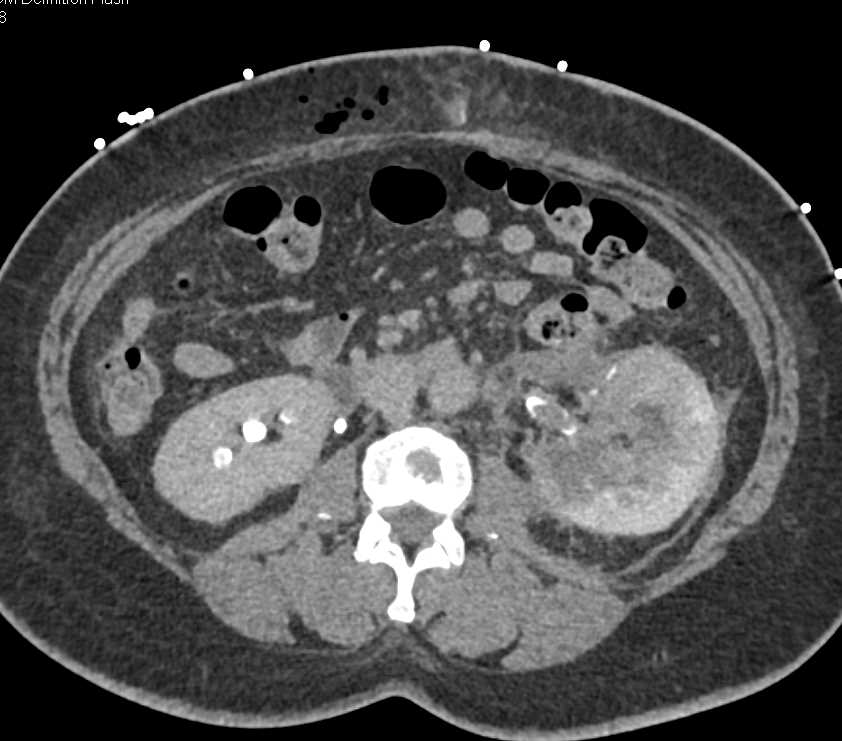

Acute Pyelonephritis Right Kidney